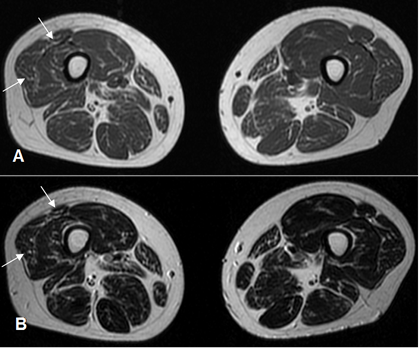

Fig 29 C. Atrofia Muscular.

A: RM axial en T1 y B: RM axial en T2. Disminución del tamaño e incipiente degeneración grasa, en los componentes del cuadriceps derecho, con predominio en el recto intermediario y vasto externo.